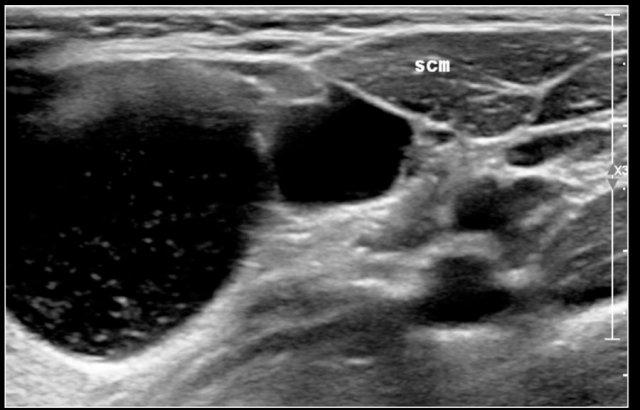

Đây là hình ảnh siêu âm của một bé gái sáu tuổi với tình trạng sưng đột ngột ở cổ bên trái.

Có nhiều nang nhỏ không có âm vang và một nang lớn chứa các âm vang bên trong, có thể là kết quả của xuất huyết trong một u bạch huyết mạch có sẵn từ trước.